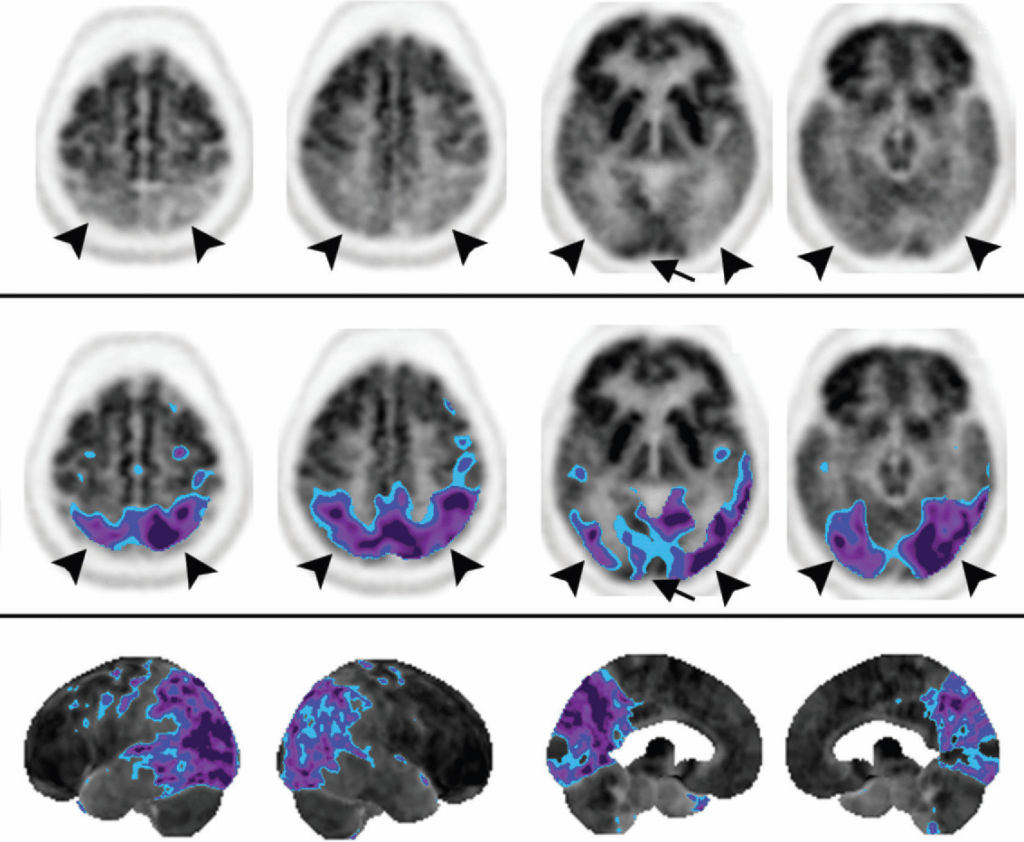

Il pattern classico della Malattia di Alzheimer è caratterizzato da un ipometabolismo che coinvolge tipicamente il giro del cingolo posteriore, il precuneo e i lobi parietali e temporali posteriori. Il coinvolgimento del giro del cingolo posteriore è un segno quasi costante e spesso il primo a manifestarsi. Le alterazioni possono essere asimmetriche. Le aree tipicamente risparmiate nella malattia di Alzheimer includono la corteccia sensomotoria, la corteccia visiva, il giro del cingolo anteriore, i gangli della base, il talamo e le strutture della fossa posteriore. Nelle fasi avanzate, l’ipometabolismo può estendersi alle cortecce associative prefrontali, ma il cingolo anteriore rimane preservato.

Demenza a Corpi di Lewy (DLB)

La DLB presenta un pattern di ipometabolismo simile a quello dell’AD, con interessamento parieto-temporale posteriore. Tuttavia, la DLB è caratterizzata da un segno patognomonico che ne permette la differenziazione: il coinvolgimento aggiuntivo dei lobi occipitali, inclusa la corteccia visiva primaria, con un metabolismo relativamente preservato a livello dei lobi temporali mediali e della corteccia cingolata posteriore. Quest’ultima caratteristica prende il nome di “cingulate island sign” (segno dell’isola cingolata). Questa caratteristica è altamente specifica e permette di distinguere la DLB dalla Malattia di Alzheimer, in cui la corteccia visiva è tipicamente risparmiata.

Demenza Fronto-Temporale (FTD)

La Demenza Fronto-Temporale si manifesta con un ipometabolismo localizzato nei lobi frontali e temporali anteriori, con un coinvolgimento caratteristico anche del giro del cingolo anteriore. Questo aspetto rappresenta un importante fattore di differenziazione rispetto all’AD, in cui il cingolo anteriore è invece risparmiato. Esistono varianti della FTD, come la variante a predominanza frontale (associata a cambiamenti comportamentali) e la variante temporale (o demenza semantica), caratterizzata da disturbi del linguaggio.